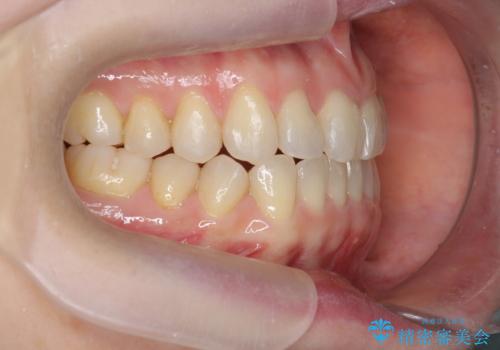

前歯の目立つガタつきをマウスピース矯正で治療

- 大きく傾いてしまった前歯のガタつきの改善を求めて来院されました。

前歯のガタつきをしっかりと取り、機能的・審美的に理想的な歯並びをマウスピース矯正で達成します。

強度のガタつきはマウスピース単体では並び切ることが難しいこともありますが、しっかりと装着していただいたことで良好な治療結果を得ることができました。